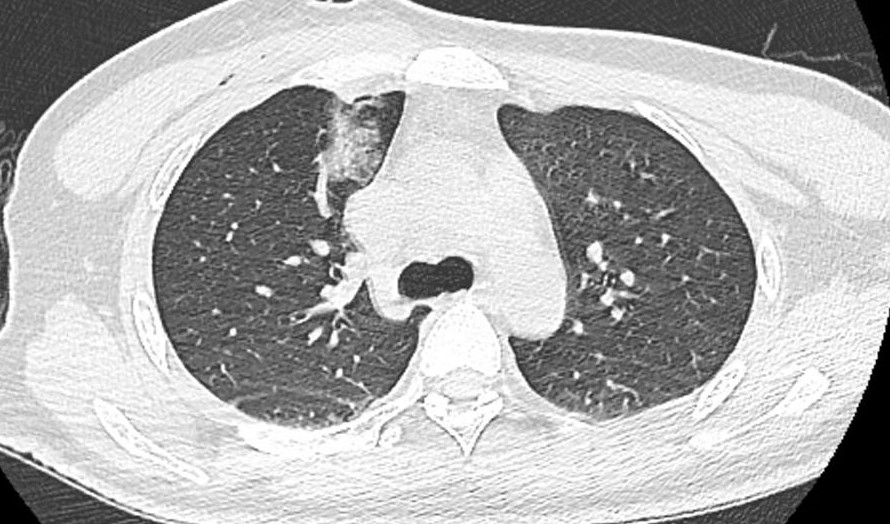

(箭头所指出:术前右肺上叶磨玻璃结节,周围可见分刺征)

针对临床上各类肺结节诊疗问题,独墅湖医院特别安排了肺结节多学科会诊(MDT)门诊,解决广大患者就医问题,门诊由呼吸科与危重症医学科蒋军红主任、胸心大血管外科马海涛主任、放射科郭亮主任、介入与血管外科程龙副主任医师等知名专家联合坐诊。针对谢先生的情况,专家们共同查阅了谢先生的CT图像,其结节周围有分刺征象,CT表现倾向于早期肺癌,考虑微浸润癌向浸润癌进展,且谢先生目前十分年轻,建议早日治疗。但是谢先生有慢性肾脏病病史,高血压控制不佳,考虑谢先生传统手术风险高,建议谢先生行CT引导下活检+微波消融手术。